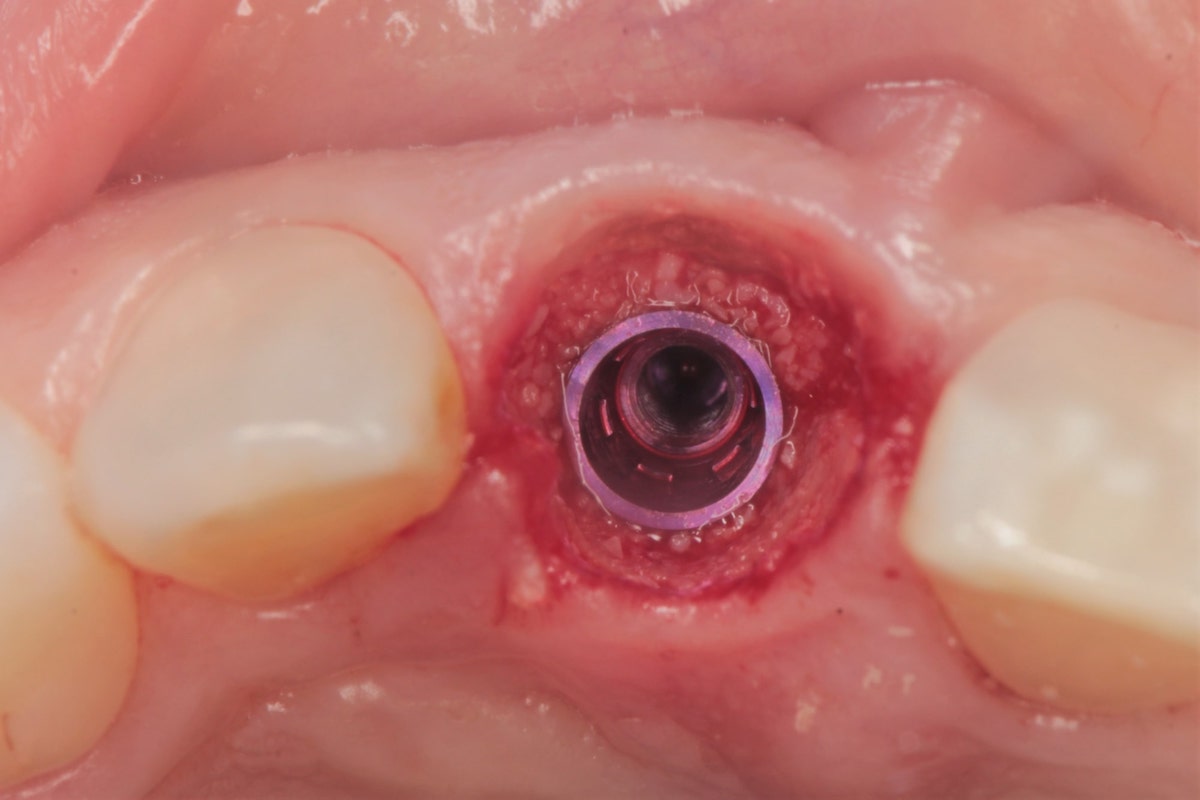

Implantacje natychmiastowe to zabiegi wszczepiania implantów bezpośrednio bo zabiegu ekstrakcji zęba. Umożliwiają wprowadzenie implantu w miejsce po usunięciu zęba podczas jednej wizyty. Bardzo często implantacja natychmiastowa nie wymaga dodatkowego cięcia, gdyż wykorzystywana jest luka w wyrostku zębodołowym powstała po wyrwaniu zęba.

Jeżeli lekarz nie widzi żadnych przeciwwskazań ogólnoustrojowych oraz istnieją dobre warunki podłoża kostnego, można od razu po ekstrakcji przeprowadzić zabieg implantacji. Warunkiem wykonania natychmiastowego wszczepienia implantu jest odpowiednia jakość i wielkość wyrostka zębodołowego.

Natychmiastowe wszczepienie implantu hamuje zanik kości, procesy zachodzące po utracie zębów, ale również zapewnia komfort ze względów estetycznych i praktycznych.

Gojenie się podłoża kostnego z wykorzystaniem materiału kościozastępczego zwykle następuje w okresie od 3 do 6 miesięcy. Jest to okres osobniczo zmienny, ponieważ u każdego pacjenta proces regeneracji kostnej zachodzi inaczej. Kluczowe w tym okresie osteointegracji są wizyty kontrolne, podczas których implantolog ocenia stan gojenia się kości. Na każdej wizycie wykonywane jest zdjęcie RTG, które umożliwią tę ocenę. Prawidłowo wygojone podłoże kostne kwalifikuje pacjenta do zabiegu implantacji.